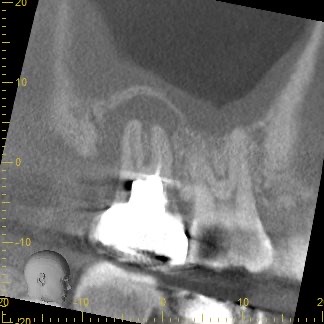

3ヶ月経過後のCT画像です。

術前のCT画像と比較すると、歯根周囲の黒くなっていた部分の骨の回復を認めました😊

ここまで回復すれば長期的な安定期が期待できるため、被せ物を作製していきます。